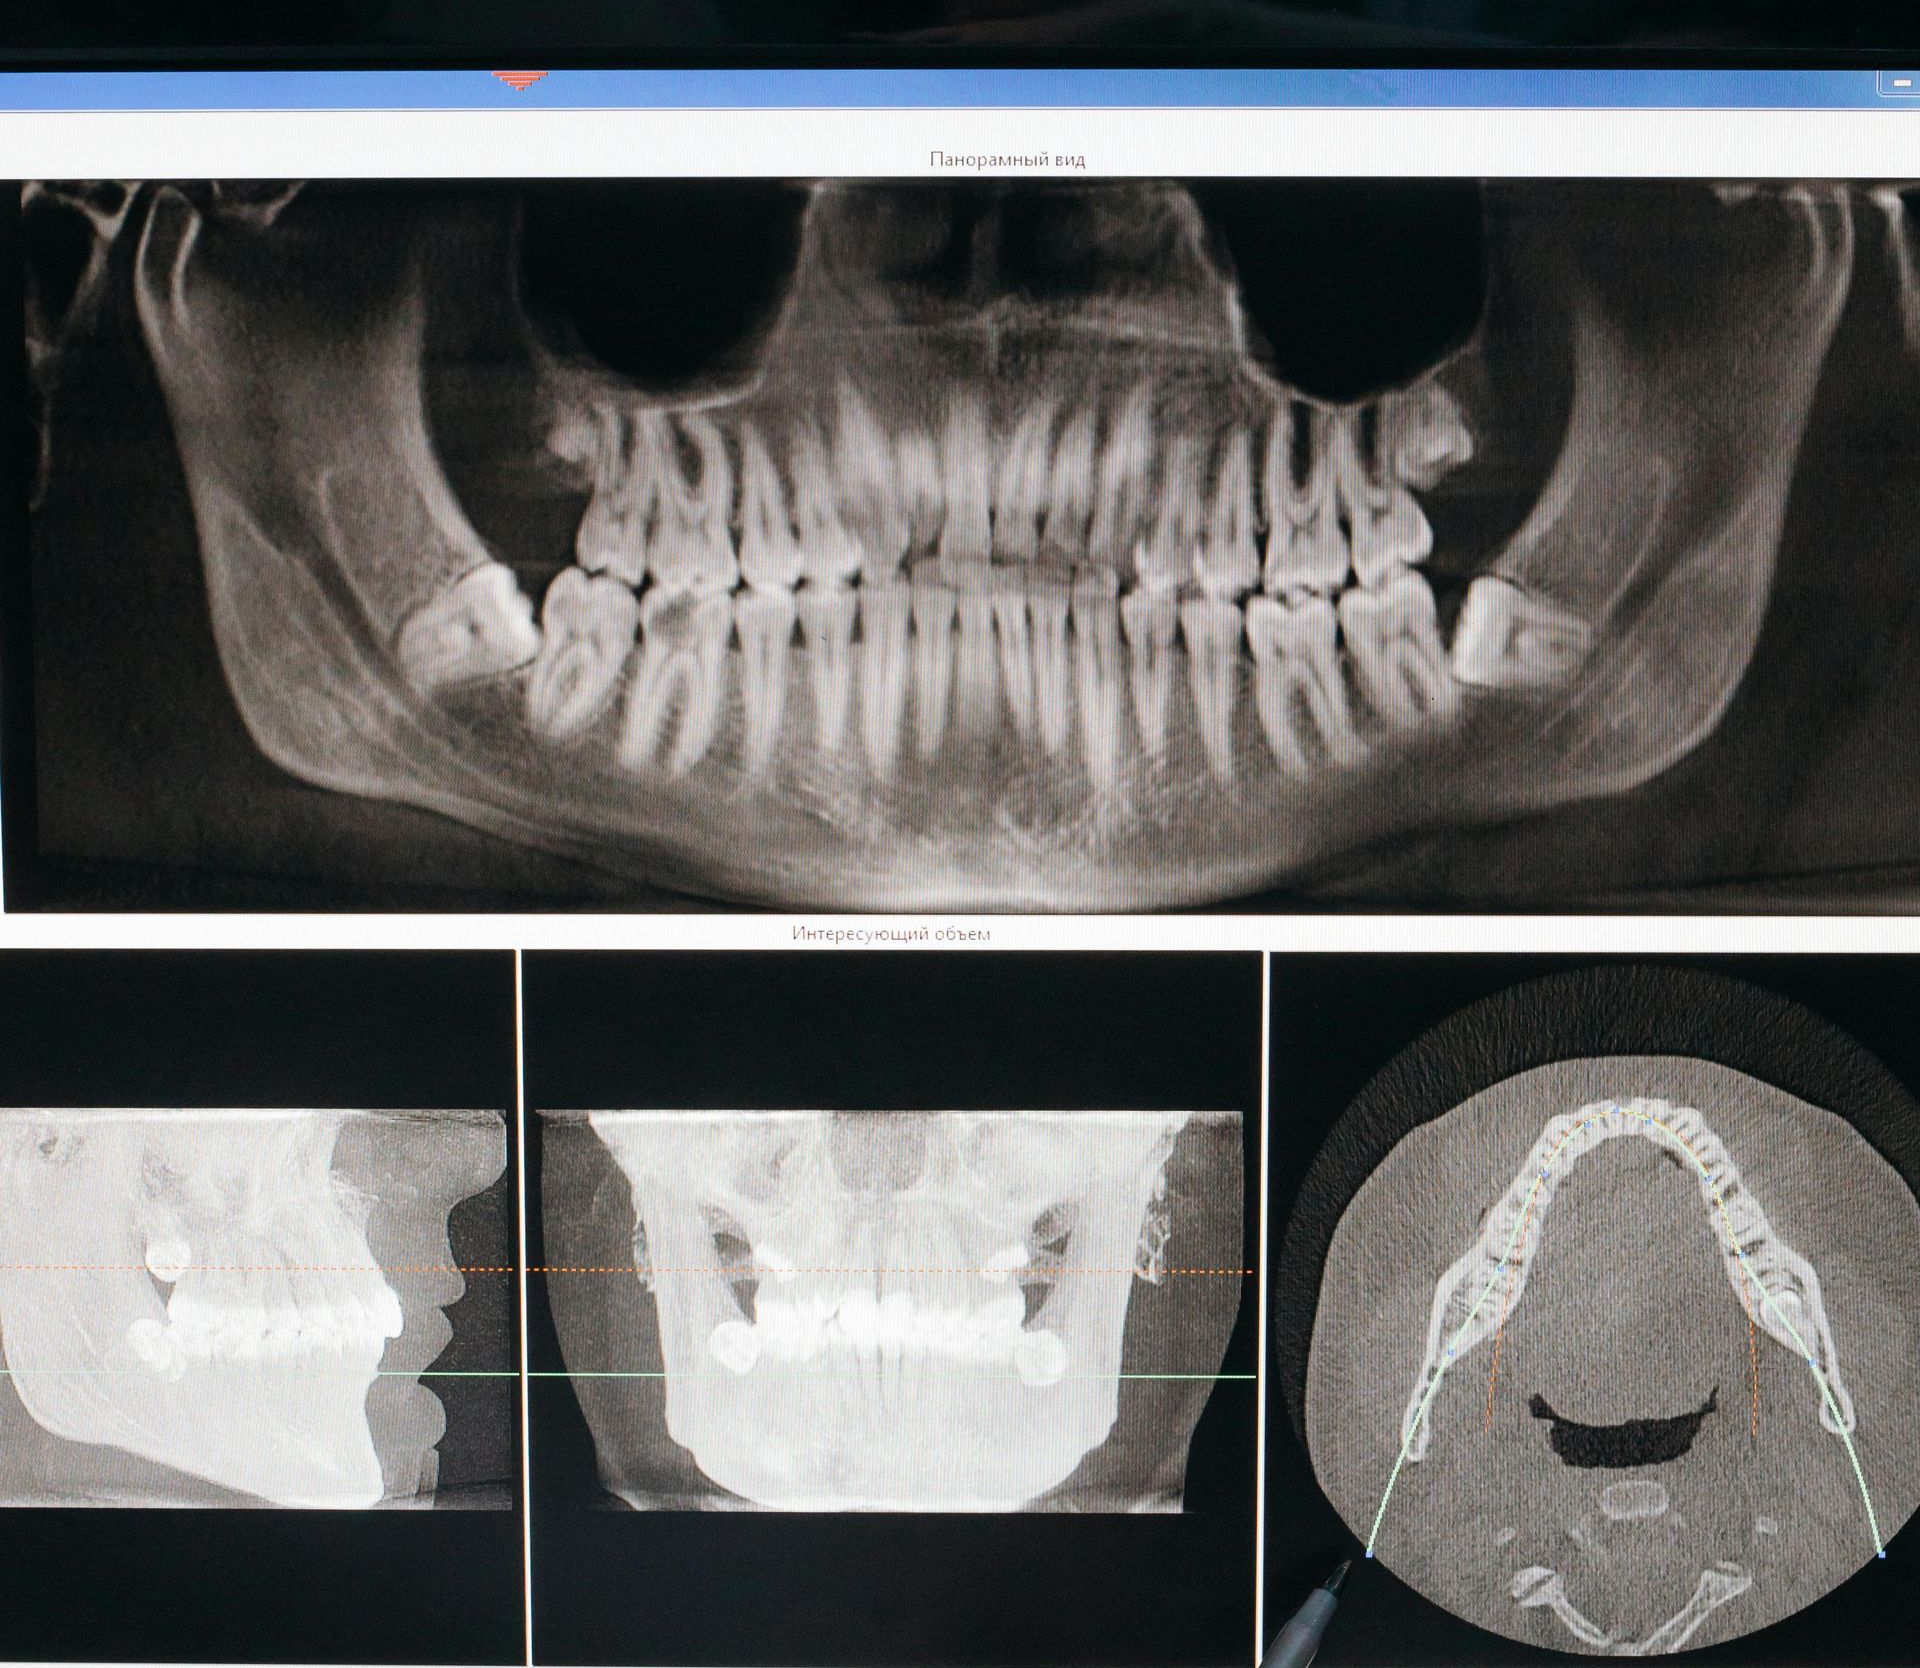

Cone Beam 3D Imaging (CBCT)

How It Works

The Cone Beam creates a detailed 3D image of your teeth, jawbone, sinuses, and nerves, allowing for more accurate diagnosis and treatment planning.